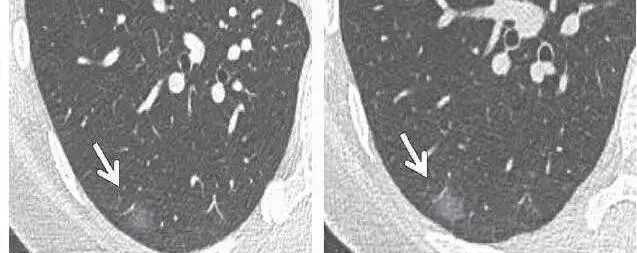

对于磨玻璃影,我们首先要结合患者的其他病史、症状、累及范围进行综合判断,如果判断是急症,那么需要积极进行治疗;如果判断是慢性病变,同时没有办法确定性质,那么最为主要的还是进行随访观察,也就是通过随访观察确定其性质。比如一些磨玻璃结节,第一次发现的时候没有办法确定性质,那么通过随访观察往往都是可以确定性质的。

对于肺结节,我们第一步首先也是通过影像学来判断其良恶性,如果是有比较典型的恶性征象,无论是实性结节、磨玻璃结节还是混合密度结节,最后的治疗办法都是进行手术切除;而如果是比较小的微小结节,第一次检查没有办法确定其性质,那么这个时候最为主要的办法还是进行随访观察,通过随访判断其性质。通常来说,良性结节随访过程中是不会增大的,可能一直没有变化,也可能不断缩小、甚至消失;而恶性的结节在随访过程中会逐渐增大,同时出现一些典型的影像学征象。

而一旦随访发现有恶性倾向,也要第一时间进行手术切除治疗;而如果提示良性,则一般不需要进行特殊的治疗。